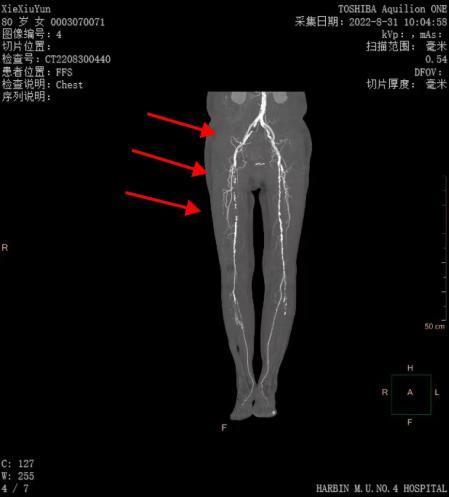

哈醫(yī)大四院血管外科完成省內(nèi)首例準(zhǔn)分子激光消蝕減容術(shù)治療下肢動(dòng)脈硬化閉塞癥

聽說過激光能祛斑、祛疤、治近視眼,您聽說過激光還可以通血管么?日前,哈醫(yī)大四院血管外科應(yīng)用準(zhǔn)分子激光設(shè)備,率先在省內(nèi)成功為一位高齡下肢動(dòng)脈硬化閉塞癥患者開通閉塞血管,完成我省首例應(yīng)用準(zhǔn)分子激光消蝕減容術(shù)治療下肢動(dòng)脈硬化閉塞癥的手術(shù)。謝大娘今年80歲,半年前自覺右下肢疼痛,麻木,皮溫涼,跛行距離100米,未進(jìn)行治療。半月前疼痛加重,出現(xiàn)患足靜息痛,跛行距離僅為10米,且夜間疼痛明顯加重,嚴(yán)重影響生活質(zhì)量。家屬帶謝大娘來到哈醫(yī)大四院血管外科,黃任平主任接診后通過下肢動(dòng)脈CTA發(fā)現(xiàn)患者右側(cè)股總動(dòng)脈、股淺動(dòng)脈閉塞,考慮患者癥狀明顯,如不進(jìn)行手術(shù)干預(yù),缺血加重可能會(huì)導(dǎo)致肢體壞疽,截肢可能。經(jīng)過縝密的術(shù)前討論,黃任平主任決定采用我院剛剛引進(jìn)的準(zhǔn)分子激光設(shè)備為患者開通病變血管。黃任平主任團(tuán)隊(duì)為患者實(shí)施手術(shù),通過左側(cè)股動(dòng)脈穿刺翻山至右側(cè),導(dǎo)入準(zhǔn)分子激光導(dǎo)管,對閉塞動(dòng)脈血管進(jìn)行消融,消融后即刻可見血管恢復(fù)通暢。然后導(dǎo)入藥物涂層球囊擴(kuò)張,再次血管造影可見股腘動(dòng)脈通暢,血液流速快,術(shù)后患者足背及脛后動(dòng)脈搏動(dòng)恢復(fù),右下肢靜息痛消失,跛行癥狀明顯緩解,目前患者已經(jīng)康復(fù)出院。黃任平主任介紹,準(zhǔn)分子激光消蝕術(shù)(ExcimerLaserAtherectomy,ELA)是一種在歐美國家常規(guī)使用的冠脈介入治療手段,應(yīng)用準(zhǔn)分子激光治療下肢動(dòng)脈硬化閉塞癥在國外已經(jīng)開展多年,在我國開展較晚,該手術(shù)在我省尚屬首例。其原理是在光化學(xué)作用下,斑塊組織對308nm激光能量的吸收可引起分子鍵的斷裂,碎化成直徑小于25um的碎片,因此該準(zhǔn)分子激光可以安全消蝕溶解血管內(nèi)的血栓、斑塊等組織,更有效的開通閉塞的血管,同時(shí)能夠保證開通血管的遠(yuǎn)期通暢率,減少了支架的植入。該技術(shù)適合在下肢動(dòng)脈硬化閉塞癥,血栓閉塞性脈管炎,以及支架再閉塞等嚴(yán)重下肢缺血患者治療中應(yīng)用。?????????????專家簡介??????????????????????黃任平醫(yī)學(xué)博士、博士后,碩士生導(dǎo)師哈爾濱醫(yī)科大學(xué)附屬第四醫(yī)院血管外科主任???專業(yè)方向:擅長血管外科的常見病多發(fā)病的診治,從事微創(chuàng)血管病治療與創(chuàng)面治療10余年,治愈各種靜脈曲張、糖尿病足、下肢靜脈血栓、脈管炎、動(dòng)脈硬化閉塞癥、胸腹主動(dòng)脈瘤、動(dòng)脈栓塞、肺栓塞、鎖骨下動(dòng)脈閉塞、腎動(dòng)脈狹窄、嬰幼兒血管瘤、血管畸形等20000余例。出診地點(diǎn):哈爾濱醫(yī)科大學(xué)附屬第四醫(yī)院門診三樓C區(qū)外科3診室咨詢電話:0451-82576869